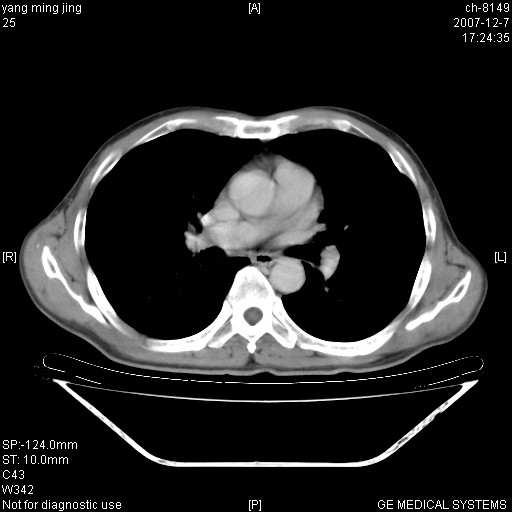

以下是引用zsl6918在2007-12-7 22:22:00的发言:[br]左肺上叶中心性肺癌并肺内及纵隔淋巴结转移,肝内转移。小细胞肺癌可能性大。

以下是引用狙击手在2007-12-8 11:03:00的发言:[br]考虑:左肺上叶中心性肺癌并肺内及纵隔淋巴结转移,肝内转移。